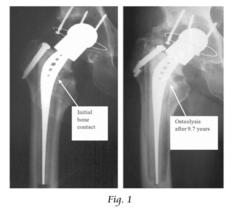

The mechanical property customization capabilities of VAM materials constitute another breakthrough area. Through precise control of crosslinking density, filler content, and microstructural features, materials can now be tailored to match the specific mechanical requirements of different anatomical locations. This addresses the long-standing issue of mechanical mismatch between implants and surrounding tissues, which often leads to stress shielding and eventual implant failure.